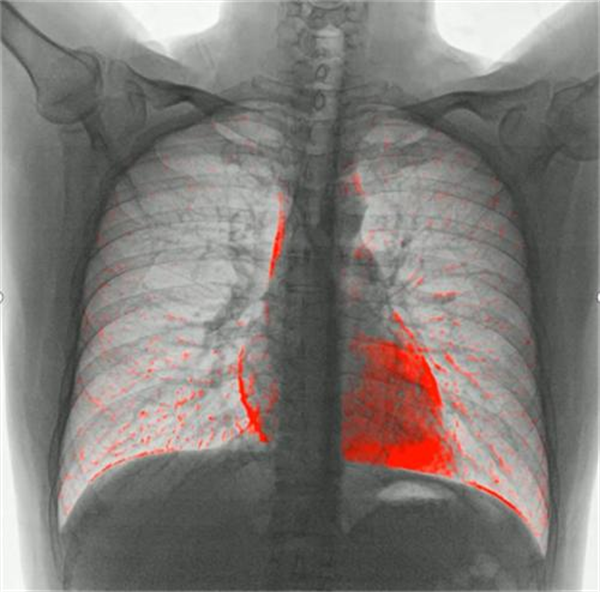

动态DR不仅在三维化成像技术上有着创新性突破,还在功能成像技术上有着独特的优势,尤其是在胸部、骨关节与腹部成像检查中,动态 DR 具有其无可比拟的优势。在肺功能上的应用,可以通过测量呼吸流速、流量分析、肺部通气功能分析等,直观的展现出患者呼吸过程中的通气异常区域,对通气异常及COPD患者提供影像学诊断全新的技术手段。对肺部进行血流灌注分析,来实现在无造影剂条件下对肺栓塞进行评估。还可以应用于骨骼运动方向研究,例如颈椎运动功能成像,骨折修复后愈合状态的评估等。(第一张图为肺部血流灌注成像,第二及第三张图为颈椎运动功能成像)